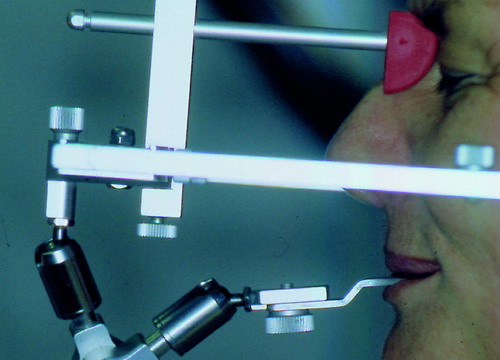

LA OCLUSIÓN MUTUAMENTE PROTEGIDA ES UN VIEJO CONCEPTO QUE CONSISTE EN LA MUTUA INTERACCIÓN DE LOS DISTINTOS GRUPOS DENTARIOS ENTRE SI. DE ESTA FORMA, LA TABLA PREMOLAR / MOLAR DE AMBOS HEMIMAXILARES ANTAGONISTAS, DETIENEN EL CIERRE MANDIBULAR EN CÉNTRICA, LOS CANINOS DISCLUYEN LAS PIEZAS POSTERIORES DURANTE LAS TRANSTRUSIONES, Y EL GRUPO INCISIVO LO MISMO DURANTE LAS PROPULSIVAS. SIN EMBARGO, DICHO CONCEPTO ES LIMITADO A LAS PIEZAS DENTARIAS, SIN TENER EN CONSIDERACIÓN LA IMPORTANTE FUNCIÓN QUE RECAE SOBRE LA ATM Y EN EL SOPORTE DE PRESIONES DURANTE ESTA DINÁMICA. ES ASI QUE EN EL AÑO 1981, EL DR. ANIBAL ALONSO GENERA EN LA CIUDAD DE BUENOS AIRES UN CONCEPTO MAS AMPLIO QUE DENOMINÓ : OCLUSION MUTUAMENTE COMPARTIDA. REF I EN EL QUE AMPLÍA EL CONCEPTO ANTERIOR, HACIENDO PARTÍCIPE A LA ATM EN LA MISMA. CUANDO EXISTE CARENCIA DE PIEZAS DENTARIAS POSTERIORES, YA SEA DE UN SOLO LADO O DE AMBOS , EL CIERRE MANDIBULAR ES DETENIDO POR LAS PIEZAS RESTANTE, FORZANDO A LA ATM A SOPORTAR PRESIONES MUY SUPERIORES A AQUELLAS PARA LAS QUE ESTA PREPARADA. FIG1 FIG2 FIG3 LUEGO DEL ESTUDIO CLÍNICO DE RIGOR, DONDE SE EVALÚA RADIOGRÁFICA Y PERIODONTALMENTE, SE PROCEDE A TOMAR MODELOS DE ESTUDIO Y MONTAR EN ARTICULADOR SEMIAJUSTABLE, SOBRE EL CUAL SE REALIZA UN ENCERADO PROGRESIVO DE DIAGNÓSTICO, A PARTIR DEL CUAL SE CONFECCIONA UN JUEGO COMPLETO DE PROVISIONALES DE AMBAS ARCADAS , INCLUYENDO LAS PIEZAS FALTANTES. SE ABORDA EL CASO YA QUIRÚRGICAMENTE DONDE EN UNA PRIMERA ETAPA SE TALLAN PRIMARIAMENTE LAS PIEZAS DENTARIAS Y SE PROCEDE, EXODONCIANDO EL INCISIVO CENTRAL SUPERIOR DERECHO, A REALIZAR UNA ROG(REGENERACIÓN ÓSEA GUIADA), PARA INMEDIATAMENTE INSTALAR PARTE DE NUESTROS PROVISORIOS EN LA GUIA ANTERIOR. SE ADAPTAN A LOS SECTORES POSTERIORES LAS PRÓTESIS REMOVIBLES QUE PORTABA, Y SE ESPERAN CUATRO MESES, AL CABO DE LOS CUALES SE REALIZA UN ESTUDIO CON DENTASCAN, MEDIANTE EL USO DE UNA FÉRULA RADIOLÓGICA CON TUBOS METÁLICOS , QUE NOS SERVIRÁ TAMBIÉN DE GUÍA QUIRÚRGICA. PROCEDEMOS ENTONCES A LA IMPLANTACIÓN DE LOS SECTORES EDÉNTULOS MEDIANTE IMPLANTES ROSCADOS Y TÉCNICA SEMI SUMERGIDA. TRANSCURRIDAS OCHO SEMANAS OBSERVAMOS UNA CORRECTA SALUD PERIMPLANTARIA, Y REALIZAMOS LA INSTALACIÓN DE LOS ABUTTMENTS ALCANZAMOS ENTONCES EL PUNTO EXACTO DONDE DEBEREMOS COMENZAR A RECONTRUIR EN FORMA PERMANENTE. PAZ DEL SISTEMA: CENTRICIDADARTICULAR-PAZ MUSCULAR-ESTABILIDAD- -ACOPLAMIENTO. BASES FUNDAMENTALES DE LA OCLUSIÓN ORGÁNICA FIG41 FIG42 PROCEDEMOS NUEVAMENTE A TOMAR IMPRESIONES, EN ESTE CASO DEFINITIVAS , MONTAR NUEVAMENTE EN ARTICULADOR, Y CONSTRUIR LAS RESTAURACIONES PERIFÉRICAS TOTALES EN BASE A PORCELANA SOBRE ORO GALVANIZADO. REF. II SOBRE LAS MISMAS TERMINADAS Y YA EN BOCA, CHEQUEÁMOS TODOS LOS ELEMENTOS QUE CONSTITUYEN UNA REHABILITACIÓN ORAL INTEGRAL, DESDE LA SALUD ENDODONTICA DE PIEZAS TRATADAS O NO, LA SALUD PERIODONTAL, EL AJUSTE PERIFÉRICO DE LAS RESTAURACIONES, LA ESTABILIDAD EN LA ATM, Y LAS FUNCIONES OCLUSALES, CHEQUEOS ESTOS QUE SE REPETIRAN EN CADA UNO DE LOS CONTROLES POST OPERATORIOS. FIG46 FIG47 FIG48 FIG66 FIG67 REFERENCIAS: REF I: OCLUSIÓN Y DIAGNÓSTICO EN REHABILITACIÓN ORAL REF. II ELECTROFORMACIÓN EN ODONTOLOGÍA RESTAURADORA.